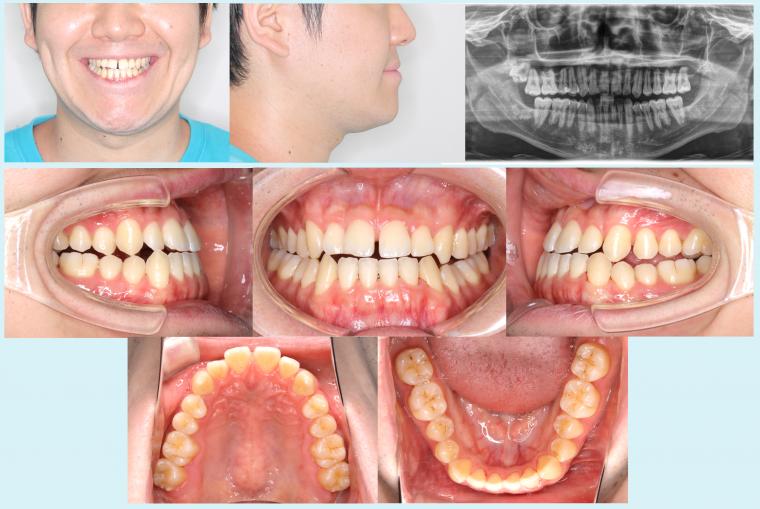

#46 下顎歯列の後方移動を行った症例